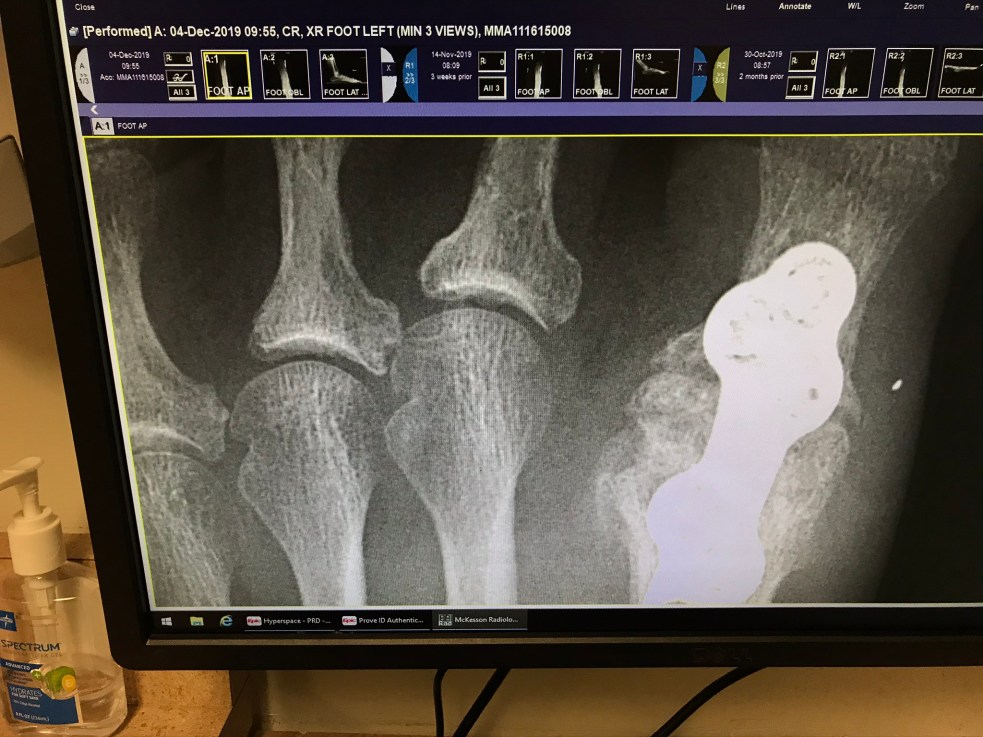

Returned to the foot surgeon because I was clueless. The toe he put a steel plate in a few years ago (with six lovely screws) seems to be rising up again. Arthritis had made that toe begin to stick up in the first place. He went in during surgery, removed the bone, shaved it down, turned it over. Screwed it down with the plate. He showed me on the current x-ray that it cannot rise up as the bone tissue has grown over the plate now. But respecting how it feels to me, he ordered a CT scan of that toe.

Then for more bad news. To correct my toe with the loose screws the only option is surgery. The procedure would be more complicated this time than it was 5 years ago. He would have to take out all the hardware as the bone has calcified over most of it.

For right now I will get new orthotics on August 26. With the new orthotics I will try walking in an enclosed shoe after the many blister sites heal. They will then decide if I need new shoes. If there is no improvement, the doctor might want to do surgery sooner rather than later. For now, I have time to decide when. Yes, it would require 8 weeks on knee roller again, no weight bearing. When he told me I thought I might puke. The last surgery, after 6 weeks, I was ready to hurt the surgeon. I am 5 years older now and not at all eager to take this on.

I believe eventually the plate and screws that are in there will have to be removed. Next time for repair he would use 2 plates and more screws. He would also shorten the tendon in toe next to great toe. I asked how he would do that. Did not like that answer either. He would snip the tendon. WHAT?!?!?